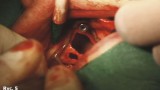

Pacjentka wyraża zgodę na zabieg chirurgiczny, polegający na wprowadzeniu wszczepów podokostnowych, zdając sobie sprawę, że jest to ostatnia deska ratunku, umożliwiająca stabilne zakotwiczenie protezy wspartej na wszczepach. Po zabiegu implantacji dwie oddzielne siatki podokostnowe (ryc. 3) zostaną ze sobą połączone (ryc. 4). Podniesiony płat śluzówkowo okostnowy (ryc. 5) ukazuje zgodność anatomii tkanki kostnej z modelem stereolitograficznym. Pozabiegowe zdjęcie pantomograficzne (ryc. 6) obrazuje idealne połączenie między dwiema siatkami, umieszczonymi precyzyjnie na swoim miejscu. Mezostruktura (ryc. 7) jest odpowiednim podparciem dla docelowej protezy typu „U” (ryc. 8).